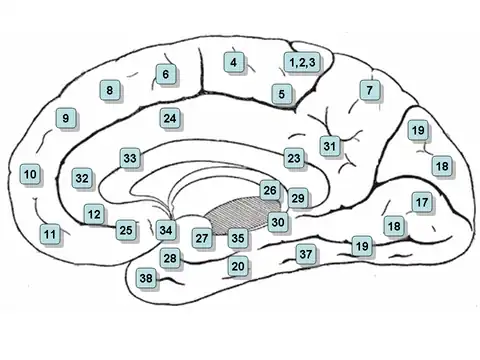

Medial surface of the brain with Brodmann's areas numbered. | |

Area 27 of Brodmann-1909 is a cytoarchitecturally defined cortical area that is a rostral part of the parahippocampal gyrus. It is commonly regarded as a synonym of presubiculum.[1]

The dorsal part of the presubiculum is more commonly known as the postsubiculum[2] and is of interest because it contains head direction cells, which are responsive to the facing direction of the head.[3]